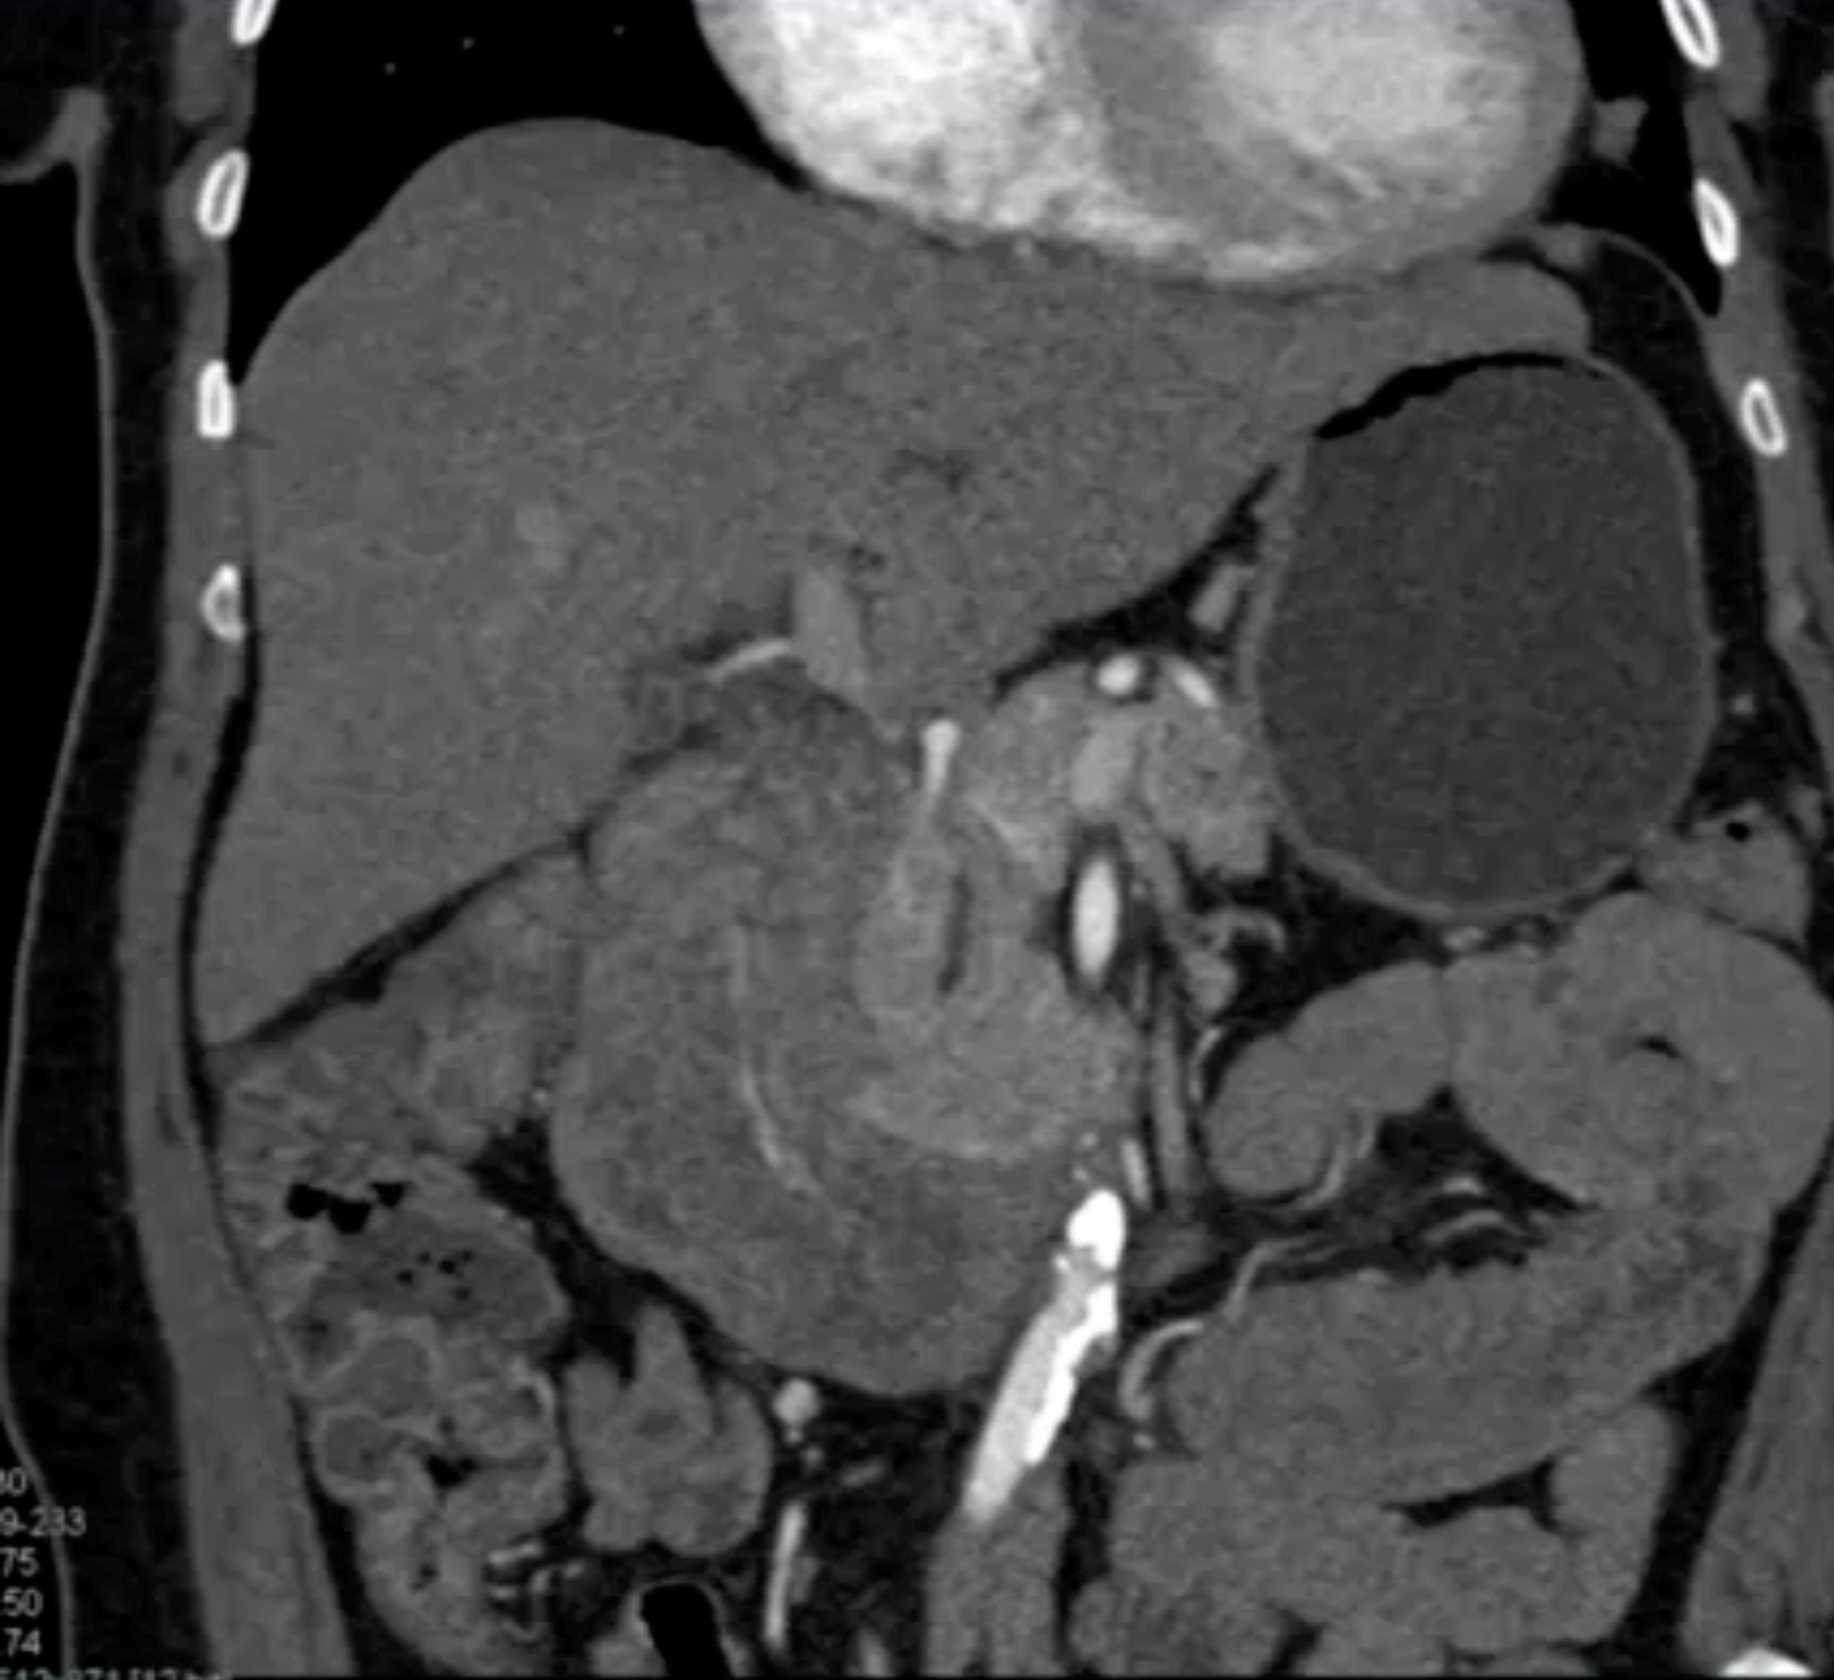

Lagre Gastric GIST Tumor